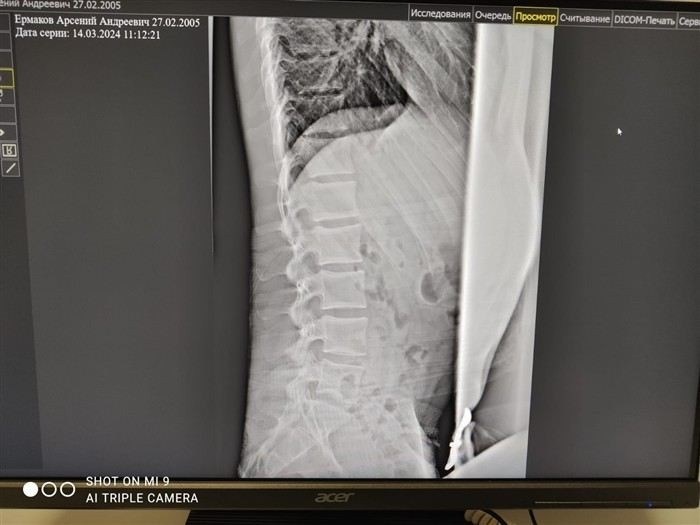

Мужчины, страдающие остеохондрозом, должны предоставить всю необходимую медицинскую документацию, включая заключения врачей, результаты рентгенологического обследования и других специалистов. Рентген снимки позволяют точно определить степень изменений в позвоночнике, а заключения невролога и терапевта могут подтвердить наличие болевого синдрома и его влияние на повседневную жизнь. Окончательное решение по году призыва принимается на основании этих документов.

Призывник должен понимать, что для оценки состояния спины важен не только субъективный отчет о болях, но и объективные данные, такие как рентгеновские снимки, заключения специалистов, а также информация о функциональном состоянии позвоночника. Например, кифоз или деформации, которые не вызывают болевого синдрома, но сказываются на осанке, могут повлиять на решение комиссии. На основании этих данных комиссия решает, какой категорией годности будет обладать призывник.

При сильных болях в спине и изменениях в позвоночнике важно, чтобы на руках у призывника были документы, которые точно отражают его состояние здоровья. Документы, такие как рентгеновские снимки или заключение рентгенолога, играют ключевую роль в подтверждении диагноза и тяжести заболевания. В некоторых случаях, когда болезнь имеет скрытые проявления, комиссия может назначить дополнительные обследования, чтобы точно определить степень риска для здоровья во время службы.

Для того чтобы пройти медицинскую комиссию и получить военный билет, призывнику с болями в спине необходимо предоставить целый ряд медицинских документов. В первую очередь, важны рентгеновские снимки позвоночника, которые покажут наличие или отсутствие изменений в структуре костей и суставов. Рентгенология поможет установить степень остеохондроза, кифоза или других заболеваний позвоночного столба. Эти данные позволят точно определить, какие ограничения следует установить для службы в вооружённых силах. В некоторых случаях комиссия может потребовать дополнительные исследования, например, МРТ или консультацию невролога, чтобы исключить скрытые осложнения, которые не видны на рентгене.

При решении комиссии для службы проверьте несколько ключевых факторов, связанных с состоянием здоровья призывника. В первую очередь, комиссия основывает своё решение на степени выраженности болей в спине и возможных ограничениях, связанных с ними. Проблемы с позвоночником, такие как остеохондроз, кифоз или межпозвоночные грыжи, требуют особого внимания. Для принятия решения комиссия ориентируется на медицинские документы, включая заключения врачей и рентгеновские снимки. Эти данные помогают определить, в какой степени заболевание ограничивает физическую активность и способность выполнять военные обязанности.

Заболевания позвоночника могут проявляться различными симптомами, начиная от лёгкой боли до сильных болей, сопровождающихся функциональными нарушениями. Например, кифоз, сколиоз или остеохондроз шейного отдела могут привести к ограничению подвижности и даже к головным болям. Сверьте степень заболевания и наличие осложнений. Если изменения в позвоночнике выражены, это может повлиять на решение комиссии. В случае скрытых заболеваний, которые не всегда видны при внешнем осмотре, обязательным является рентгенологическое обследование.

На решение комиссии влияет и такой фактор, как наличие скрытых заболеваний, которые могут быть не выявлены при первичном осмотре. В таких ситуациях комиссия может назначить дополнительные обследования, например, провести рентгеновское исследование, которое позволит более точно оценить изменения в позвоночнике. Если результаты обследования подтверждают наличие серьёзных нарушений, решение комиссии будет направлено на освобождение от призыва или отсрочку от службы.